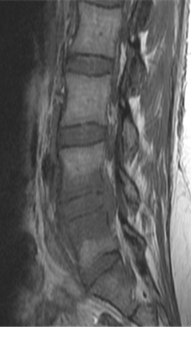

At presentation she had severe paraspinal spasm with movement restriction and no neurological deficits. Radiographs revealed a minimal reduction in L4/5 disc space . Hematological evaluation elevated showed TLC, ESR, CRP. MRI showed evidence of discitis at L4/5 with adjacent vertebral reactive changes( FIG 1,2). With a working diagnosis of post partum spondylodisctis she underwent a septic screening ( sputum, urine, blood cultures) and a CT guided biopsy which turned out to be negative. Considering her significant back pain  with limitations in suggesting antibiotics  she was suggested surgical debridement and fusion at L4/5. She underwent PLIF L4/5 under GA and had a drastic early pain relief . She was mobilized on post operative day – 1 with lumbo sacral brace. Her pain reduced significantly ( VAS 2/10) which needed minimal analgesics ( once a day paracetamol 1 gm intravenous infusion )for 5 days . She was able to turn in bed and sit to nurse the child. Her intraoperative tissues sent for culture grew pseudomonas which was sensitive to cefaperazone + sulbactum. She was initiated on intravenous antibiotics for 2 weeks duration and was followed up with further 4 weeks of oral antibiotics . Radiographs revealed fusion at L4/5 at 3 months( FIG 3,4) of follow up with serological markers normalizing by 6 weeks.

Fig 1: T2 MRI – L4/5 spondylodiscitis

Fig 2: T1 MRI – L4/5 spondylodiscitis